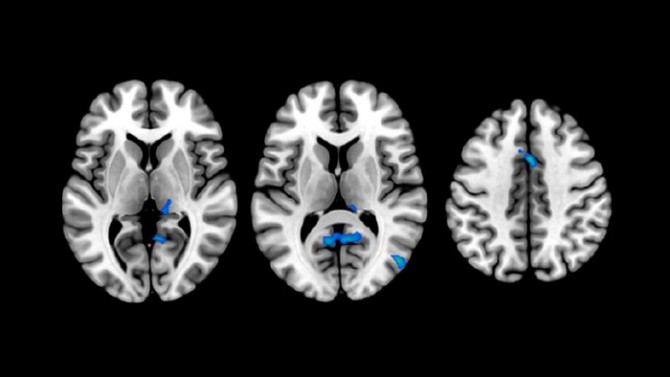

Por otro lado, el estudio demuestra, gracias a imágenes de resonancia magnética, que los participantes con insomnio presentan un menor volumen en algunas regiones cerebrales. Entre ellas se encuentran el precúneo o el córtex cingulado posterior, que se encuentran afectadas en etapas tempranas de la enfermedad. Los resultados apoyan las investigaciones que relacionan la presencia de insomnio con una elevada vulnerabilidad a la enfermedad de Alzheimer.

El presente estudio ha encontrado, además, cambios en la sustancia blanca cerebral mediante técnicas de resonancia magnética por difusión. “Estos hallazgos sugieren la presencia de procesos de inflamación cerebral que podrían tener un papel clave en la asociación entre la calidad del sueño y el Alzheimer”, destaca el Dr. Oriol Grau, primer autor del estudio. De esta forma, la publicación de estos resultados abre la puerta a una nueva línea de investigación que hasta ahora no ha sido explorada para entender la relación entre la neuroinflamación, el sueño y la demencia.

(Foto: BarcelonaBeta)